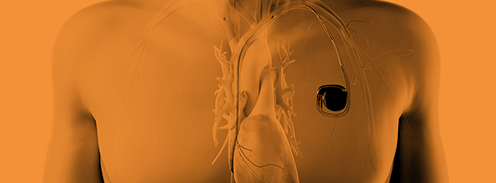

Sachkundekurs der Herzschrittmacher-Therapie Teil 1

Sachkundekurs Herzschrittmacher-Therapie Teil 2